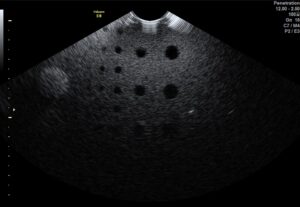

Avant la remise en huile